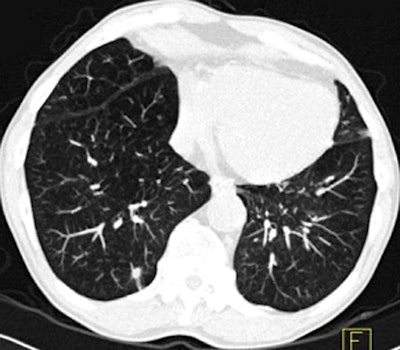

![]() |

| Images above and below show a spiculated nodule measuring 169 mm3 at baseline low-dose CT screening. Bottom image, acquired four years after the baseline scan, shows that the nodule has resolved. All images courtesy of Dr. Rosemarijn Vliegenthart. |